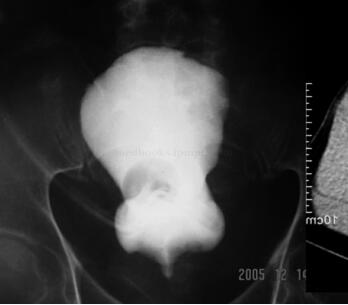

膀胱造影:膀胱拉长,明显上移(图46-1)。

图46-1 膀胱造影